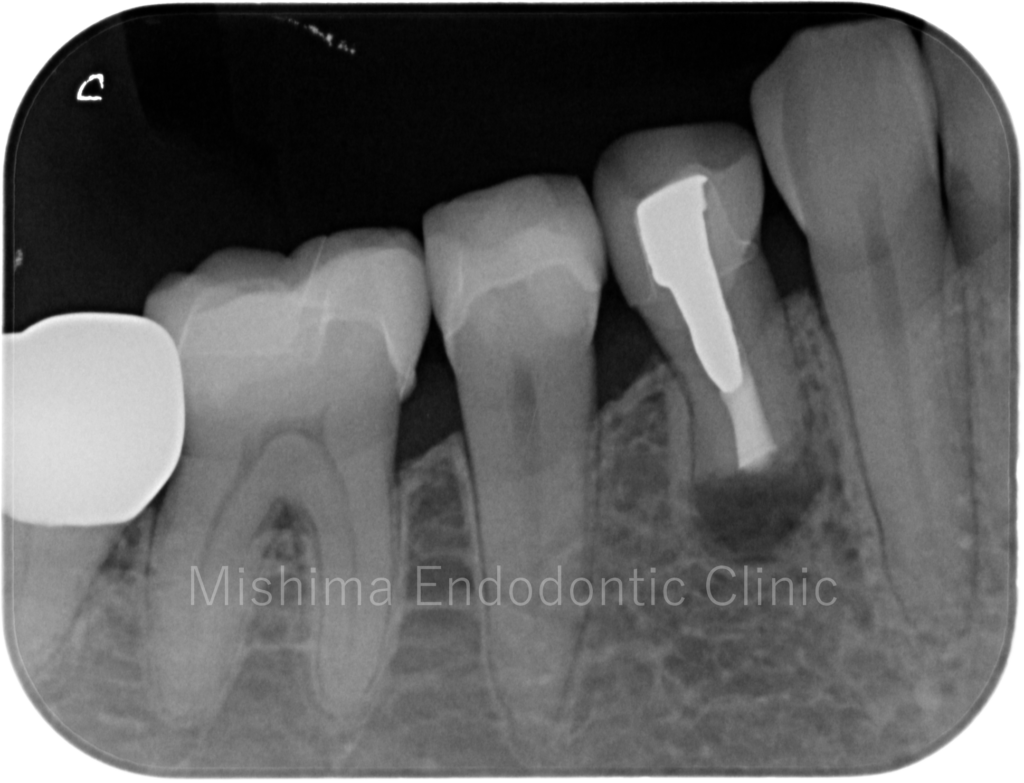

Before

| 主訴 | 以前、歯根端切除術を受けたが、痛みが出てきた。 |

| 治療内容 | 他院にて歯根端切除術の既往あり。再歯根端切除術を行い、症状、根尖透過像は消失し、経過は良好。 |

レントゲン